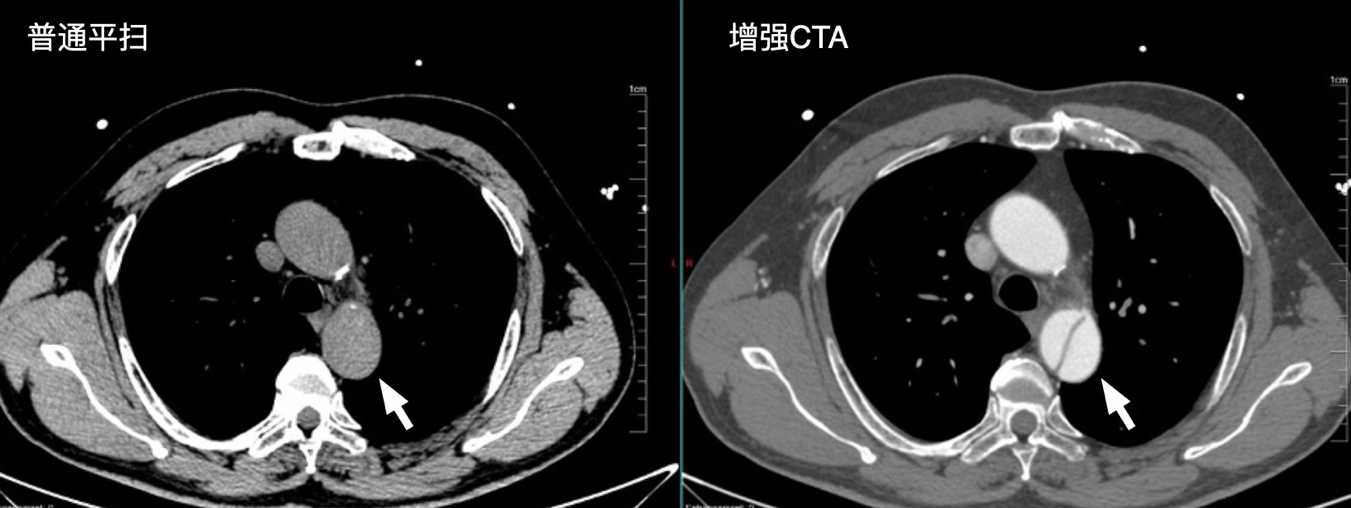

普通CT是拍的“静态”影像,比如看骨折、肺炎很方便,但遇到肿瘤、血管堵塞、肝脏病灶等问题,就像“雾里看花”——分不清病灶是良性还是恶性,也看不清血管走形。而增强CT的核心作用,就是给身体“加滤镜”:通过静脉注射碘造影剂,让造影剂随着血液流遍全身。此时CT再扫描,血管、肿瘤等组织会和正常器官组织有“色差”,医生能一眼看清病灶大小、血供情况,甚至揪出普通CT漏诊的问题。

主动脉夹层:普通平扫图和增强CTA图